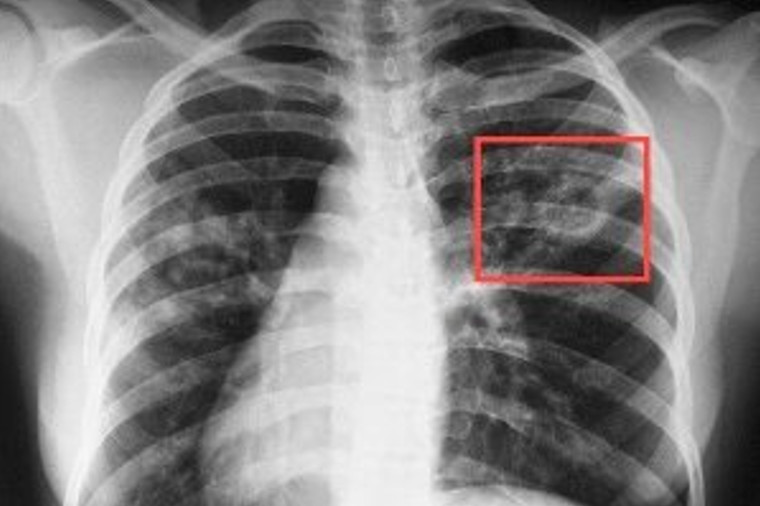

Своєчасне виявлення туберкульозу є вирішальним фактором для ефективного лікування та попередження поширення його серед людей. Чим раніше виявлено захворювання, тим більше шансів на повне одужання при умові ефективного лікування. В Україні використовуються загальноприйняті методи виявлення туберкульозу: туберкулінодіагностика (реакція Манту), флюорографічні обстеження, які необхідно проходити щорічно та лабораторні методи.